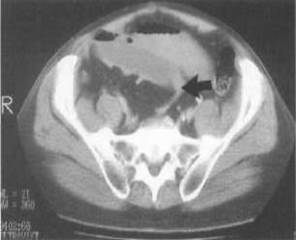

CT scanning is useful in making an early diagnosis of strangulated obstruction and in delineating the myriad other causes of acute abdominal pain, particularly when clinical and radiographic findings are inconclusive. It also has proved useful in distinguishing the aetiologies of SBO, i.e., extrinsic causes such as adhesions and hernia from intrinsic causes such as neoplasms or Crohn’s disease. It also differentiates the above from intraluminal causes such as bezoars. CT scanning is about 90% sensitive and specific in SBO diagnosis. CT scanning is the study of choice if the patient has fever, tachycardia, localized abdominal pain, and/or leukocytosis. It is capable of revealing abscess, inflammatory process, extraluminal pathology resulting in obstruction, and mesenteric ischaemia. CT scanning enables the clinician to distinguish between ileus and mechanical small bowel in postoperative patients. Obstruction is present if the small-bowel loop is greater than 2.5 cm in diameter dilated proximal to a distinct transition zone of collapsed bowel less than 1 cm in diameter (fig. 21).

Figure 21 – Note the dilated small bowel loops with a focal transition zone to distal collapsed bowel

A smooth beak indicates simple obstruction without vascular compromise; a serrated beak may indicate strangulation. Bowel wall thickening indicates early strangulation. CT scanning is useful in identifying abscesses, hernias and tumors.